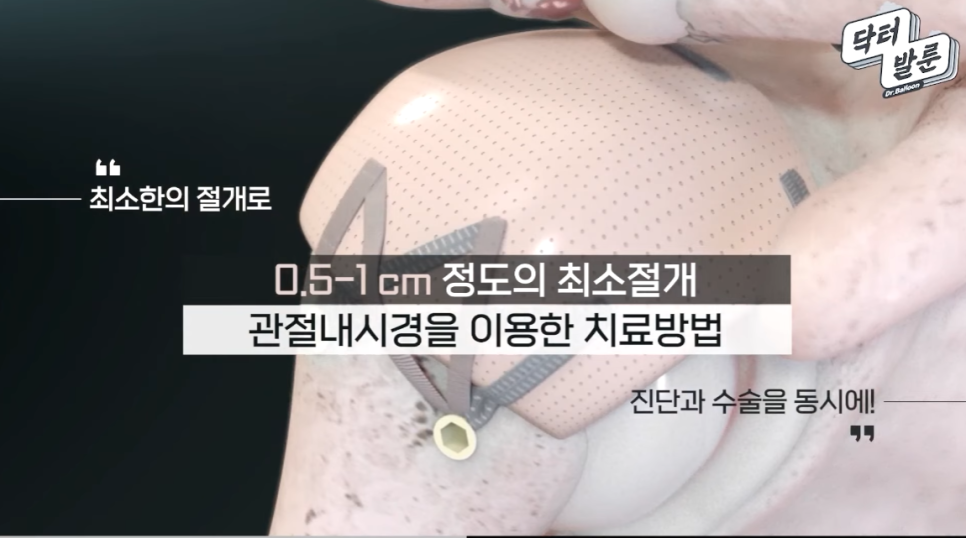

상부관절낭재건술(SCR)치료는 손상받은 어깨 회전근개 힘줄 부위에 기증받은 “동종진피(인조인대)를 이식하여, 손상된 관절을 다시 살려내고 본인의 관절을 그대로 유지하며 어깨를 정상적으로 사용할 수 있게 해주는 최소침습 관절내시경 치료”입니다.

⬆️유튜브 영상으로 확인하는 상부관절낭재건술 치료⬆️

인공관절 수술 대신, 자기의 관절을 그대로 유지하는 최소침습 내시경 치료

상부관절낭재건술은 일본의 Mihata 등이 고안한 수술법으로 최초에는 환자 본인의 대퇴근막을 허벅지에서 떼어내어 손상되어 없어져 버린 회전근개를 대신하여 어깨관절에 이식하는 치료법으로 시작하였으나, 이런 방법은 이식근막을 떼어낸 부위인 허벅지에 상처 및 통증이 추가로 발생하며, 이식건을 채취하고 다듬는데 걸리는 수술시간이 추가되고, 채취건의 질과 양을 예측하기 어려워, 최근에는 이런 자가대퇴근막을 대신하여 ⭐이식 거부반응을 제거한 동종진피(ADM; Acellular Dermal Matrix; 인공인대)를 기증받아 사용하여 내시경 상부관절낭재건술을 진행하고 있습니다.

- 절개 부위가 작아 출혈이 적고 회복이 빠릅니다.